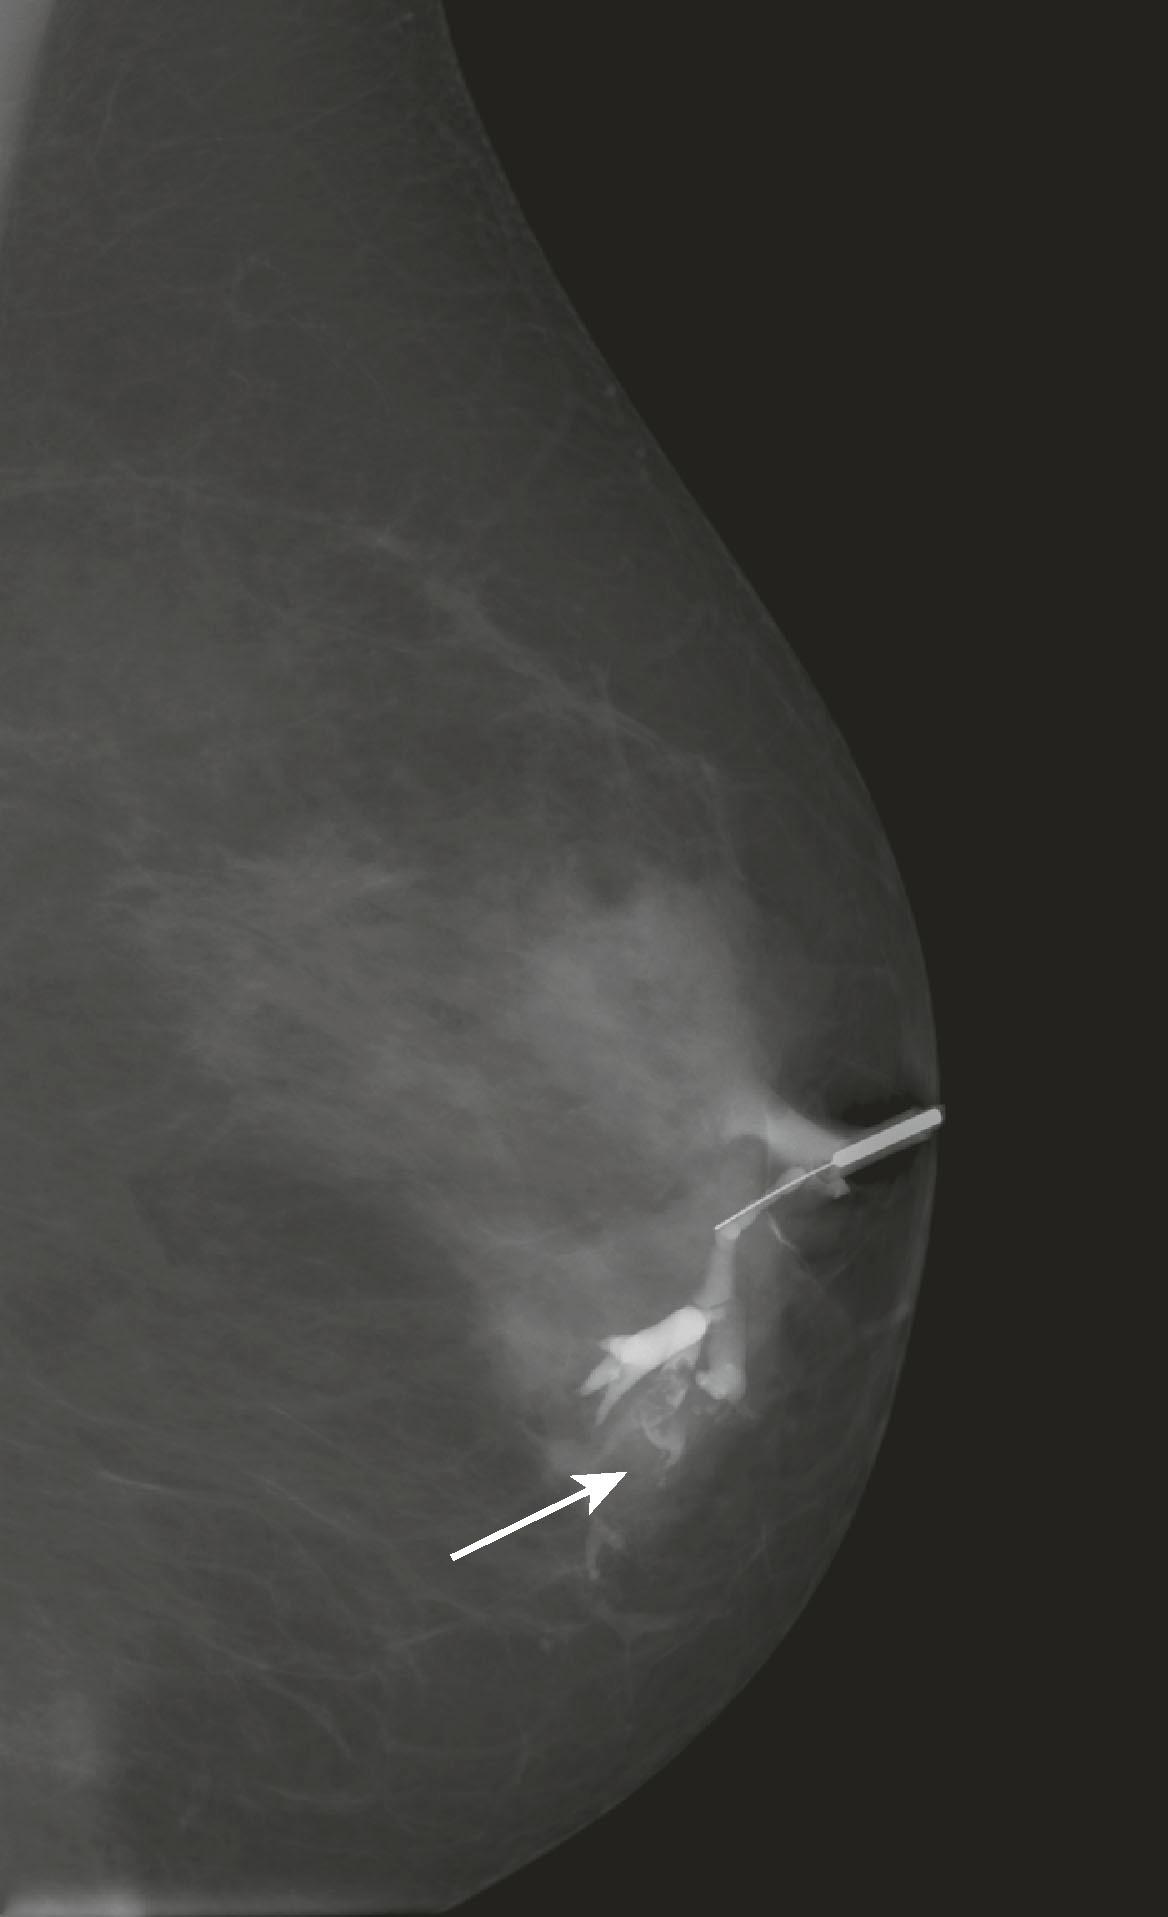

Ductography is performed to evaluate nipple discharge of clinical concern (i.e., bloody or clear to golden discharge from a single duct) to detect an intraductal pathology that is too subtle to be seen on mammography or ultrasound. A papilloma is often seen as a retroareolar lobulated filling defect, whereas DCIS may appear as a narrowed, irregularly marginated duct. Ductography is performed by cannulating the discharging duct with a 30-gauge sialogram cannula and injecting the duct with a small amount of contrast material. Mammogram views are performed with the cannula in place. The contrast opacifies the duct so that an intraluminal lesion will be visible ( Fig. 8.11 ). To identify and cannulate the proper duct, the radiologist must be able to express the discharge.

Fig. 8.11, Single ductogram image shows contrast outlining a lobulated filling defect (papilloma; arrow ).